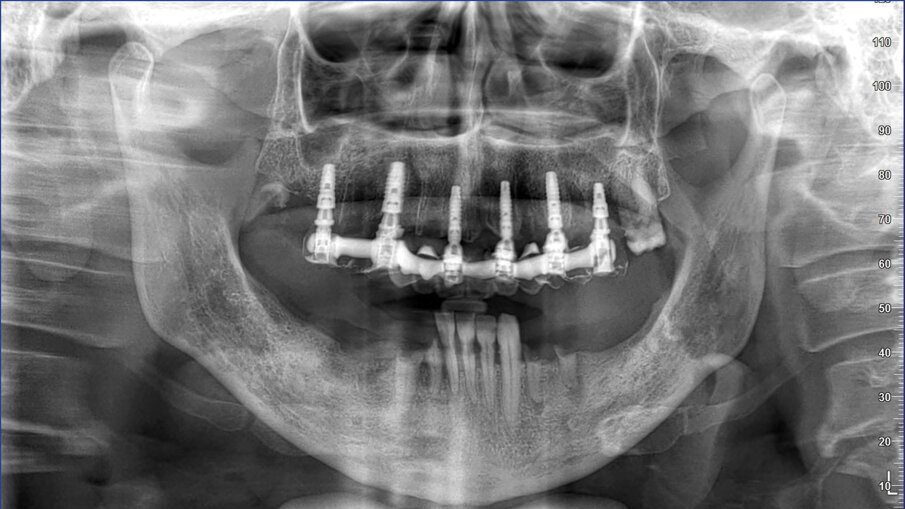

La pianificazione ha previsto innanzitutto l’allineamento all’interno del software dei file DICOM e dei file STL provenienti dalla scansione intraorale (Fig. 5). Il posizionamento degli impianti è stato ragionato in funzione di una ceratura diagnostica preventivamente realizzata con un CAD esterno e importata nel software di chirurgia guidata. Per la riabilitazione dell’arcata superiore, sono stati selezionati 6 impianti intercalati tra i siti post-estrattivi: 3,5 x 13 in posizione 11 e 22, 4 x 13 in posizione 24, 4 x 8 in posizione 26, 4 x 11,5 in posizione 14 e 4 x 10 in posizione 16. Utilizzando le informazioni dei modelli importati (master e ceratura) è stato possibile scegliere preventivamente anche le componenti protesiche in funzione delle emergenze rispetto alla ceratura e allo spessore dei tessuti (Figg. 6-8).